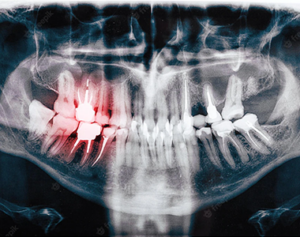

Why would I need an x-ray? Early tooth decay does not tend to show many…

With age comes wisdom. Specifically, wisdom teeth. Your mouth goes through many changes in your…